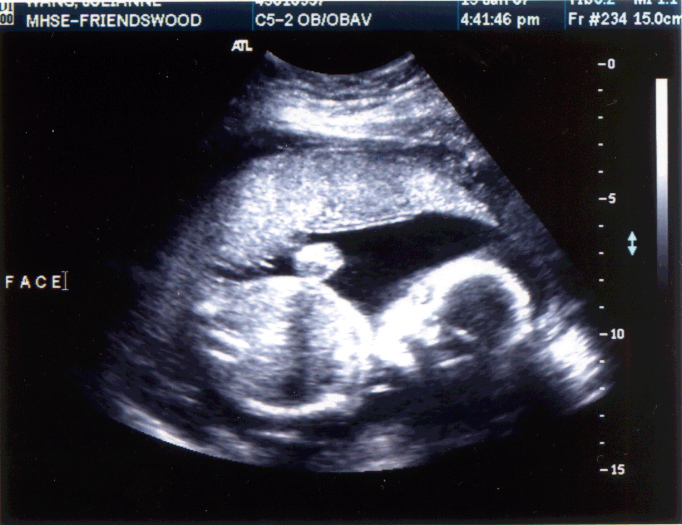

My Second Ultrasound - Baby Wang is 14 oz. on Day 1 of Week 21 of gestation, Heartbeat is 138 bpm